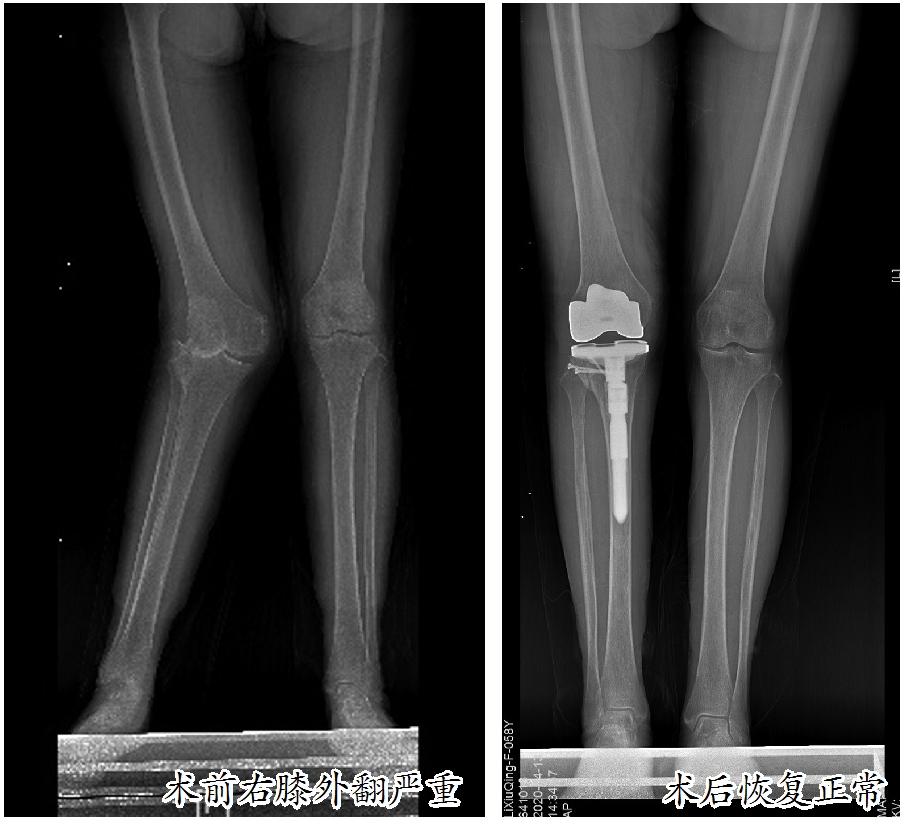

这名患者名叫李素严(化名),患有类风湿性关节炎多年,近半年感觉双侧膝关节疼痛严重,影响了日常生活,来到市人民医院骨科中心关节外科、运动医学科就诊。入院后,经过双侧膝关节X线检查发现:双膝关节存在不同程度的退行性变,其中右膝关节退化严重,重度外翻畸形,外翻角度超过30度,属于重度膝外翻,已经到了必须治疗的地步。

膝外翻又称为“X型腿”“K型腿”或“碰膝症”。在医学上,正常人的膝关节有5至7度的外翻角,如果超过此角度就是病态。膝关节向外侧倾斜10至15度为轻度外翻,超过15至30度为中度外翻,外翻角大于30度为重度外翻。

经过严密的术前准备,张新虎教授主刀对李素严实施了手术。他凭借多年的手术经验以及对膝关节结构的熟悉,在未伤及血管、神经的情况下精准完成了胫骨、股骨的截骨以及软组织松解,在检查下肢力线、膝关节屈度和伸直状态的稳定性、髌骨的运动轨迹后安装了假体。由于术前方案准备完善,术中可能出现的情况都基本得到了解决。

事实证明手术是成功的:第三天,李素严可以在家人的搀扶下慢慢下床活动了。一周后,她出院时,已经可以使用助步器独自行走了。30天后复查时,她走路已经和常人基本无异。她说:“一次手术便使我摆脱了畸形步态,我总算可以像其他人一样正常行走了”。她又恢复了往日忙碌的生活,这种忙碌是一种充实满足的感觉,笑容又回到了她的脸上。